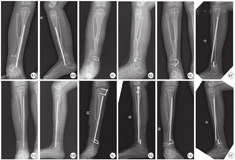

患儿术前预防使用抗生素,仰卧位后行全身麻醉,根据体重选择合适的气压止血带。开始手术前,C型臂透视下确定胫骨远端内侧骨骺位置。于胫骨远端内侧作一皮肤切口,长约3 cm,逐层显露至骨膜外,避免损伤血管和神经。根据胫骨粗细和踝外翻严重程度,选择不同长度和角度的"U"形钉植入。根据胫骨远端内侧皮质骨和骺板线的夹角,选择24°或30°的"U"形钉。通过专门的辅助植入工具,将"U"形钉平行骺板线植入(图2)。通过术中透视获得的前后位和侧位X射线照片,检查植入物位置。随后冲洗伤口,止血带放气,压迫创面及电灼止血,创面放置防粘连膜预防术后瘢痕粘连,可吸收线缝合伤口。

患儿术后每隔3~4个月复查1次,拍摄双下肢站立正位X线片,监测肢体生长和畸形矫正情况。记录每次复查的胫距角。当踝外翻畸形矫正后,考虑内固定取出。根据本团队经验,可以轻微的过度矫正外翻畸形,因为移除植入物后可能会出现一些反弹。去除内固定后,石膏固定4~6周,随后恢复全部活动。每3个月复查1次,直到骨骼成熟,监测畸形复发情况。

41例患儿术后随访至少16个月,平均随访时间为36个月。平均手术时间24 min,术中出血量平均7.5 ml,平均住院时间4.4 d。所有患儿术前胫距角为(73.9±4.4)°,去除内固定时胫距角为(86.9±4.7)°,末次随访时胫距角为(84.6±5.5)°(图3)。所有患儿去除内固定时平均矫形率为0.69°/月。"U"形钉治疗踝外翻畸形典型病例如图4、图5所示。所有患儿术后未出现螺钉脱出、骨髓炎、伤口感染等严重并发症,术后踝关节活动良好,无关节僵硬。患儿内固定拆除后未出现骺板损伤等情况。